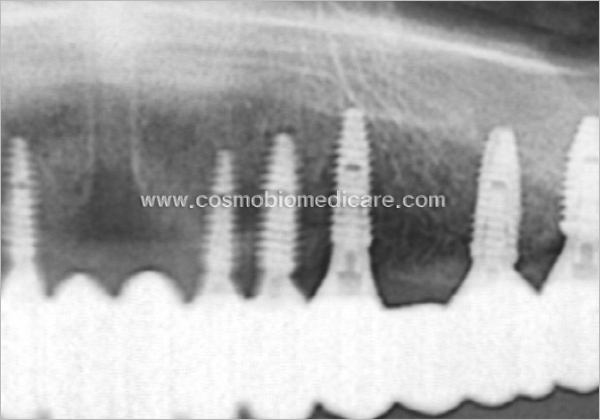

Clinical Cases

• Case1

• Case2

• Case3

• Case4

• Case5

• Case6

• Case7

• Case8

• Case9

• Case10